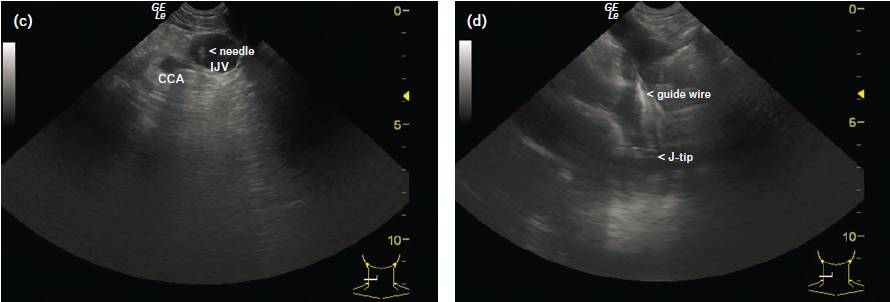

超声实时引导下留置双腔(骨科手术)或四腔(心胸外手术)CVC。微凸探头引导“平面外”静脉穿刺,通过穿刺针引导导丝置入(图1c)。导丝置入的同时经右锁骨上窝扫描SVC。调节探头以便更好地显现J型导丝尖端。逐步推进导丝,直至J型导丝尖端通过RPA的血管上壁(图1d,http://links.lww.com/EJA/A45 可观看视频,有数字内容的补充,这是一个导丝尖端定位的循环回放视频)。